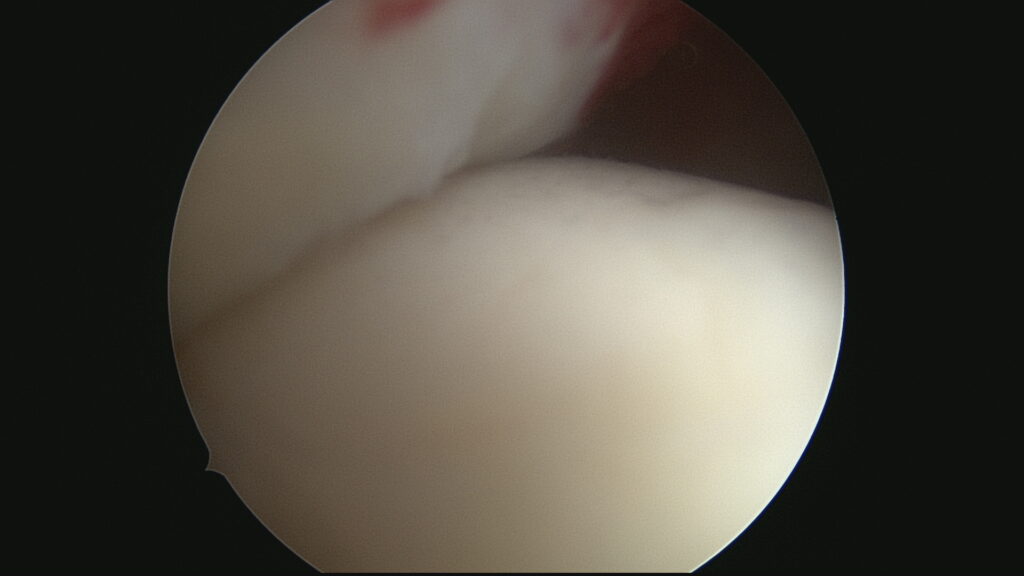

Rupture supraspinatus (Vue sous acromiale)